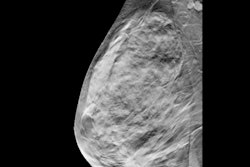

The study consisted of 121,652 screening DBT exams obtained between 2018 and 2019, which included 1,081 cancers interpreted by 15 radiologists.

Unadjusted false-positive rates fell from an average of 15.5% at the first within-batch DBT exam to 10.5% after three sequentially read exams (p < 0.001). Meanwhile, sensitivity did not significantly change between the first exam and the sequentially read exams (82.6% vs. 84.2%; p = 0.15).

Also, the interpretation time consistently decreased. This included a significant reduction in longer batches from an average of 2.8 minutes to 2.2 minutes for noncancer exams (p < 0.001).

When the researchers adjusted for sampling bias and confounding factors like patient age, breast density, day of the week, and the time of day, false-positive rates fell from 11.5% to 9.4% after three exams (p < 0.001). Finally, the same trend went for interpretation time, which decreased from 3.2 minutes to 2.7 minutes for noncancer exams (p < 0.001).